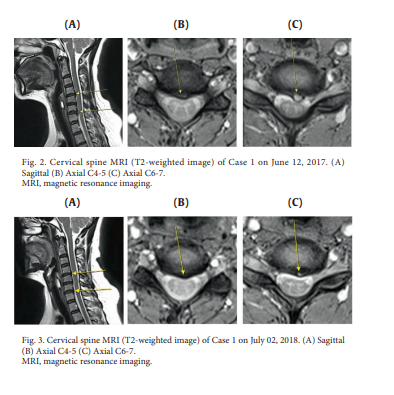

두 명의 환자가 경추 또는 요추 추간판탈출증에 대한 통합적인 한약 치료를 포함하는 침도치료를 받았습니다. 자기공명영상(Magnetic Resonance Imaging)은 치료 전후의 영상을 생성하기 위해 사용되었고, 입원 및 퇴원 시 환자를 평가하는 데 사용되는 수치 등급 척도 점수 및 운동 범위를 체크하였습니다. 두 경우 모두 자기 공명 영상에서 각각의 허리 디스크의 상당한 재흡수가 관찰되었고, 수치 등급 척도 점수가 감소했습니다. 동작 범위가 1건에서 개선되었습니다. 이 연구는 침도 치료가 탈핵성 허리디스크의 디스크재흡수 및 통증 완화에 효과적인 치료법일 수 있다는 것을 보여줍니다.

*도침치료후 재흡수된 디스크, 디스크에 침도 치료효과를 명확히 보여줍니다